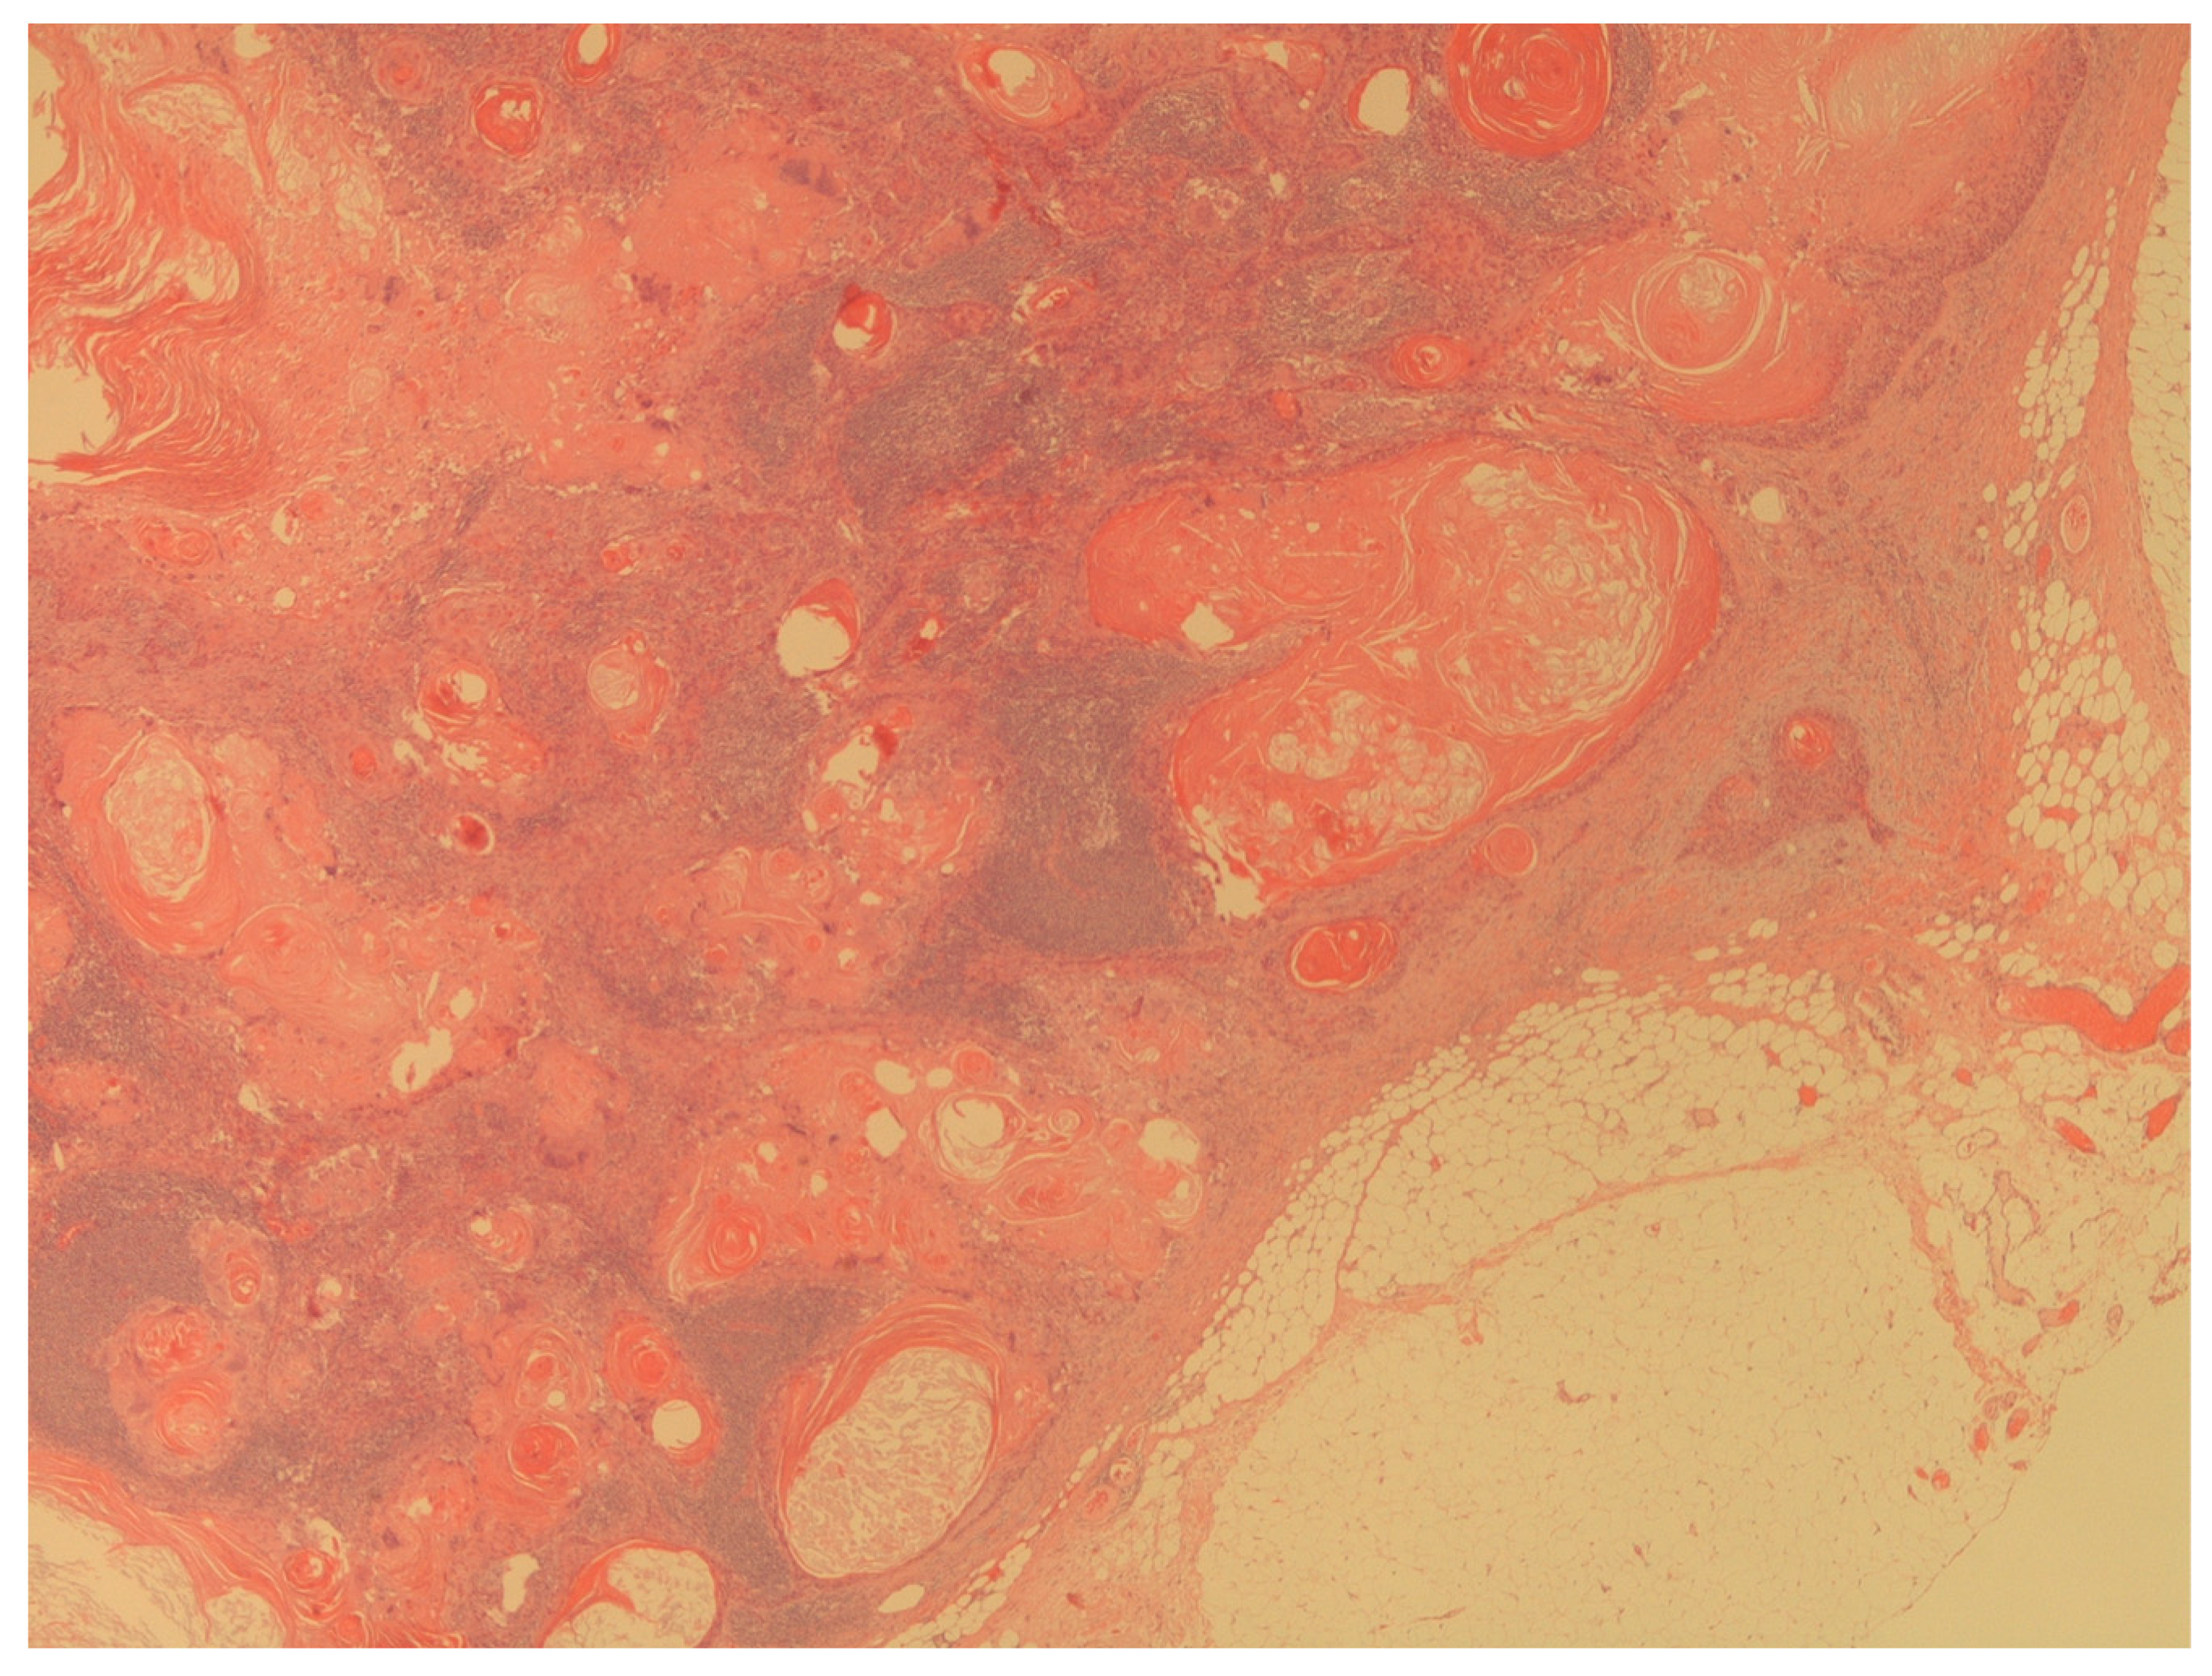

- Presence of penile cancer lymph nodes metastasis (Figure 4);

Figure 4. The figure shows a massive lymph node metastasis from squamous cell carcinoma (H&E; 20X). - -